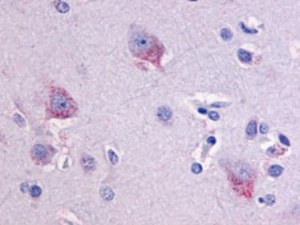

Doenças do cérebro

Todas as ferramentas necessárias para o estudo das principais doenças do cérebro, como Parkinson, Alzheimer, esclerose múltipla ...

Tumores cerebrais

Banco biológico de tumores cerebrais e ferramentas para estudar os principais marcadores destes tumores.